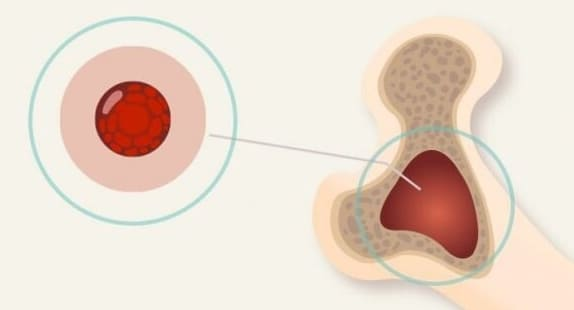

해당 사례에 의하면 백혈병에 걸린 5살 꼬마에게 골수를 기증하겠다는 사람이 등장해 꼬마는 골수이식 전 처치를 진행하게되었다.

이는 몸에다 원자폭탄을 투하하는 식으로 고용량 항암제를 투약해 문제가 있는 골수를 제거하는 작업이라고 한다.